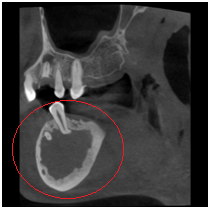

◆埋伏牙

◆牙瘤

◆由囊肿引起的骨质破坏